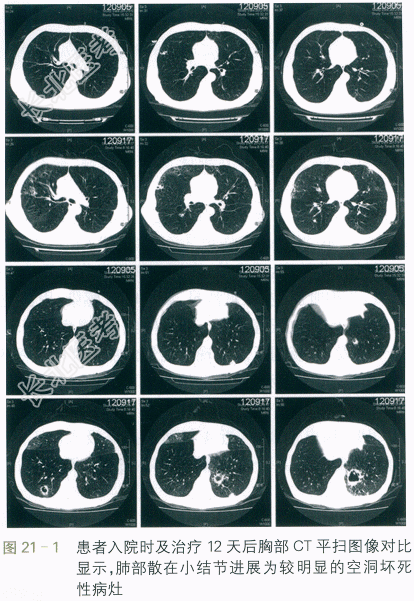

血常规:WBC9.53×109/L,N85.3%,RBC4.27×1012/L,PLT187×109/L。肝功能、肾功能正常;CRP45mg/L。不吸氧动脉血气提示pH7.43,PaCO244mmHg,PaO262mmHg。cTnT在正常范围,BNP670ng/L。入院当天胸部CT(见图21-1)提示双肺肺气肿表现,两肺少许散在结节样病灶,考虑炎性病灶可能大。心超提示肺动脉收缩压38mmHg,其余无明显异常。